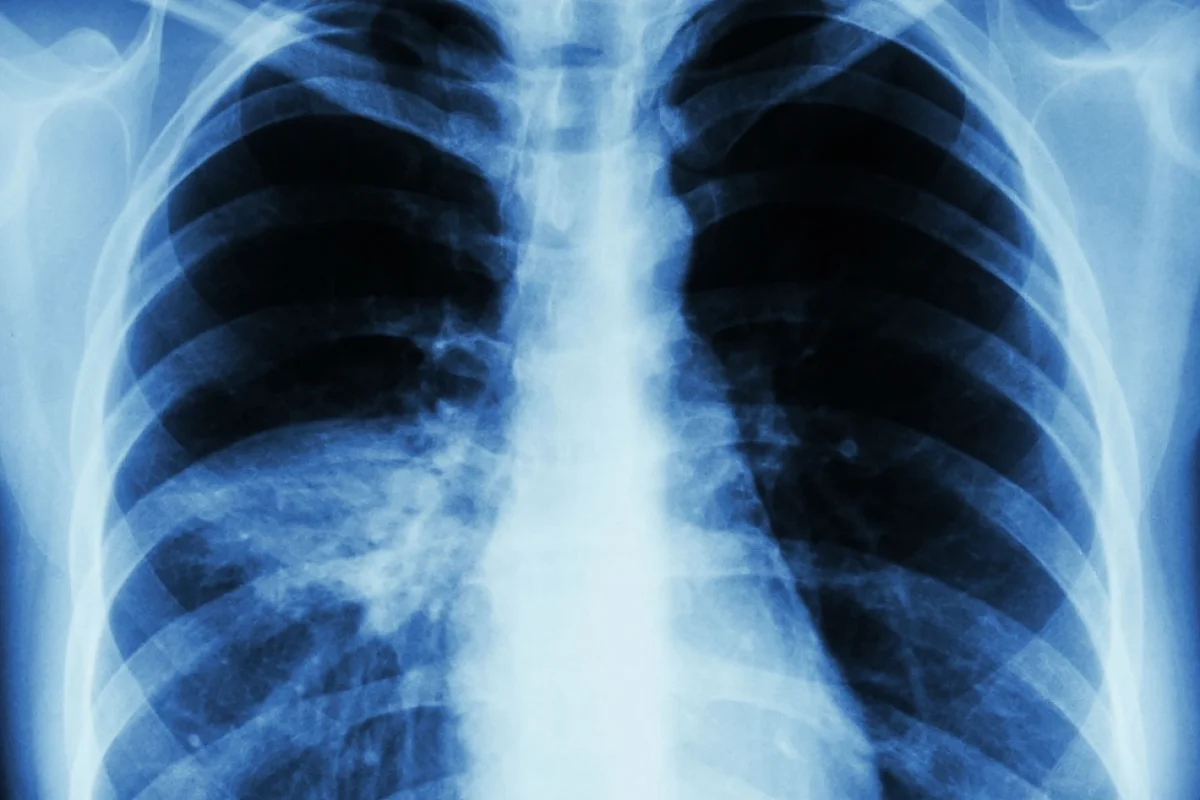

Diagnosing Central Sleep Apnea

Understanding central sleep apnea starts with a precise diagnosis. Tools like polysomnography are used. This process assesses the condition’s severity and rules out other sleep disorders.

Polysomnography Findings

Polysomnography (PSG) is key for diagnosing central sleep apnea. It records brain waves, muscle activity, and heart rate while a patient sleeps. PSG helps spot central apnea, which lacks respiratory effort, different from obstructive apnea.